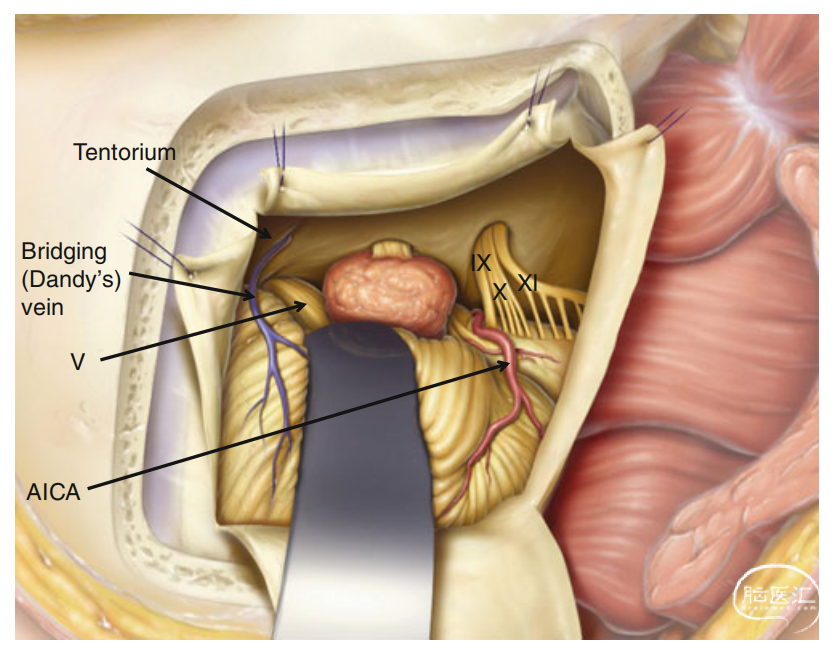

听神经瘤的保面保听手术是一种高难度的神经外科手术,通过术中面神经监测和耳蜗神经监测,旨在切除肿瘤的同时,最大限度地保留患者的面部神经(面神经)和听力功能(蜗神经)。通过该手术,患者可以在切除肿瘤的同时保留面神经和听力功能,从而提高生活质量。

复杂脑肿瘤及颅内外沟通性肿瘤的手术治疗是神经外科领域的一项具有挑战性的任务,这些肿瘤往往因其位置特殊、结构复杂、与周围组织(血管及神经)关系密切而增加了手术的难度,需要医生具备高超的手术技巧和丰富的临床经验,也常需要多学科团队的协作。我们科室常与耳鼻喉科、口腔颌面外科、头颈外科、肿瘤科等协同合作,能实现最大范围的安全切除,确保患者得到全面的治疗和护理。

7

大脑深部肿瘤由于其位置深在,周围结构复杂,给手术治疗带来了极大的挑战。脑干是生命中枢所在地,脑干肿瘤手术风险极高。大脑深部肿瘤及脑干肿瘤的显微外科手术治疗是一项复杂而精细的技术,我们通过高超的手术技巧、丰富的临床经验及一流的硬件设备,为这类患者带来个体化的精准治疗,从而达到最佳的治疗效果。